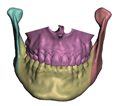

2.5.1. Bones

- In maxillary procedures, the maxilla is separated from the skull through a Lefort osteotomy, classified based on its anatomical level. In this cohort, the distribution of cases is: 8 Lefort I cases and 1 Lefort II case; one patient did not undergo maxillary surgery. Moreover, after a Lefort I osteotomy, the maxilla may be segmented (typically into three fragments) in order to expand the upper arch. Maxilla segmentation was applied to 6 patients in this cohort.

- In mandibular procedures, the mandible may be sagittally split on both rami (bilateral sagittal split osteotomy, BSSO) or only one ramus (unilateral sagittal split osteotomy, USSO). In this cohort, the distribution of cases is: 7 BSSO cases, 1 USSO case; two patients did not undergo mandibular surgery. Additionally, a chin osteotomy or genioplasty may be also performed. Genioplasty was applied to 1 patient in this cohort.